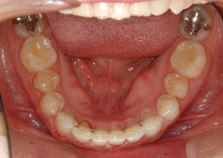

中・高校生(歯のデコボコ) 13歳

治療前(抜歯ナシ)

治療後(期間:約1年6ヶ月~2年)

①主訴:八重歯を治したい

②診断名あるいは主な症状:前歯部叢生

③年齢:13歳

④治療に用いた主な装置:マルチブラケット装置

⑤抜歯部位:写真の症例は非抜歯(かみ合わせや叢生の程度により抜歯が必要となる場合もある)

⑥治療期間:1年半~2年半

⑦治療費:検査:49,500円

基本矯正費用:880,000円~

調整料:6,600円(ひと月に1回)

⑧リスクと副作用:治療開始後数日は噛むときに痛みがあります。

虫歯や歯肉炎予防のために毎日の適切な歯磨きが重要。

装置が破損する場合があり、その時は連絡が必要

治療後には後戻り防止として保定装置が必要

歯の移動により歯根の先が溶ける場合がまれにある。